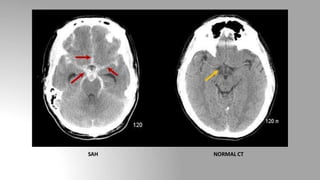

Subarachnoid hemorrhage (SAH)

• Location: Subarachnoid space

• The most common cause of subarachnoid hemorrhage is trauma

• The most common cause of non traumatic subarachnoid hemorrhage

is a ruptured aneurysm

• CT finding includes hyperdense material (instead of hypodense CSF)

within the subarachnoid space.

SAH NORMAL CT